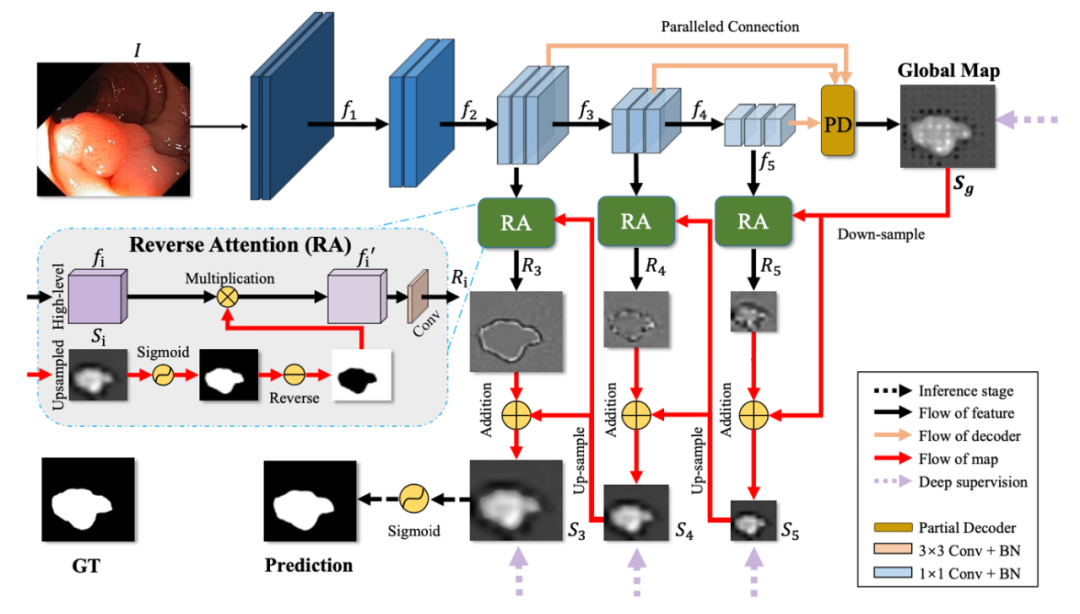

PraNet

Paper: 《PraNet: Parallel Reverse Attention Network for Polyp Segmentation》

Accepted by MICCAI 2020.

文章解读:https://cg.cs.tsinghua.edu.cn/jittor/news/2021-09-17-00-00-PraNet/

PraNet 利用并行的部分解码器在高级层中聚合特征作为初始引导区域,再使用反向注意模块挖掘边界线索,其最大贡献点在于统一了多个结直肠息肉分割任务,为后续息肉分割相关的研究铺垫了基础。